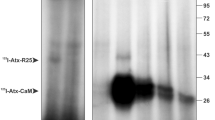

Porcine pancreatic sPLA2-IB induces neuronal apoptosis via its high-affinity binding sites in the rat brain [27]. The specific binding sites of [125I]sPLA2-IB are recognized by an anti-sPLA2R antibody. The anti-sPLA2R IgG also causes neuronal cell death as well as sPLA2-IB. By Scatchard analysis, number of maximal binding sites (B max) and dissociation constant (K d) values of [125I]sPLA2-IB is 3.1 fmol/106 cells and 0.84 nM, respectively [27]. Although 40 % of [125I]sPLA2-IB bound to neurons is displaced by 100 nM sPLA2-IB, bee venom sPLA2-III, a potent inhibitor of N-type binding sites of OS2 [80], significantly increases the binding of [125I]sPLA2-IB to neurons. The specific binding sites of [125I]sPLA2-IB are distinguishable from the N-type binding sites. sPLA2-IB appears to cause neuronal cell death via the specific binding sites, which are different from the sPLA2R and the N-type binding sites of OS2.

Human recombinant and rat spleen sPLA2-IIA causes disruption of neurites and cell bodies rather than their shrink in a different fashion to sPLA2-IB. However, as evidenced by condensed chromatin and fragmented DNA [28], ultrastructural characteristics of neuronal cell death by sPLA2-IIA are apoptotic. The M-type receptor binds toxic and non-toxic sPLA2 of either group I or II [81], giving rise to a possibility that sPLA2-IB and sPLA2-IIA might induce neuronal apoptosis via the AtxC receptor. The above two sPLA2s-induced neuronal apoptosis is suppressed by a reversible sPLA2 inhibitor, indoxam, as well as a putative irreversible sPLA2 inhibitor [28, 70]. Under the optimal conditions of each sPLA2 reaction with 1-palmitoyl-2-oleoyl-sn-glycero-3- phosphocholine as a substrate, IC50 values of indoxam against sPLA2-IIA, -IID, and -IIE are 1–2 nM [89]. On the other hand, the other isoforms (sPLA2-IB, -V, and -X) are less sensitive to indoxam with over 100-fold higher IC50 values. Indoxam does not only inhibit the enzymatic activity of sPLA2s, but also blocks the binding to its murine receptor (K i = 30 nM) [89], suggesting that sPLA2s might cause apoptosis via its high affinity binding sites and its enzymatic activity.